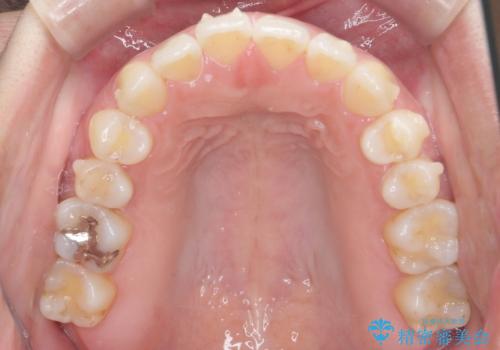

受け口、すきっ歯を インビザラインで モニター治療

- 前歯のすき間と受け口を気にして来院。

マウスピースでしっかり閉じています。

下の前歯を後方に移動するため、ゴムを上下のマウスピースにかけてもらいました。